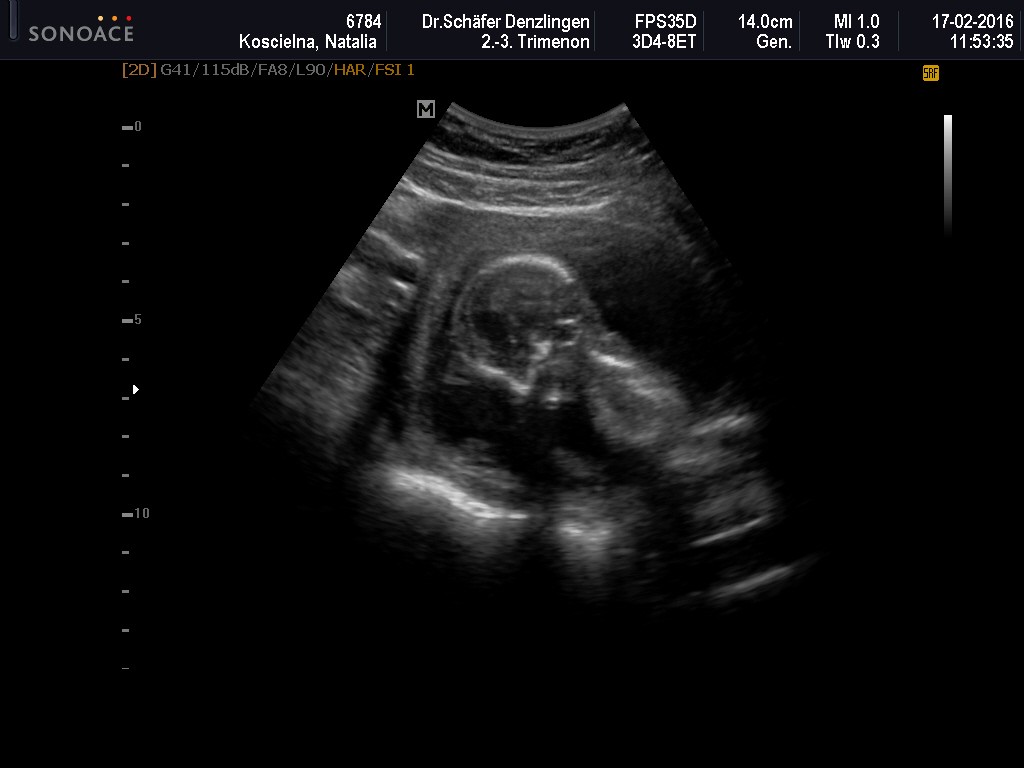

U mnie dzidzia spioch. Stwierdzil, ze nie ma tatusia, to nie pokaze nic. Nawet nie bylo co mierzyc

Za to okazuje sie, ze to juz 17 tydzien! A wg pomarow ostatnich dzic wychodzil koniec 14, takze szalenstwo. Robaczek wazy juz 140g.

Doktor powiedzial, ze z racji iz jestem szczupla, jak bobas prostuje nozki, to moze mi sie tak wypinac, ze powstaje taka pilka.

Najwazniejsze, ze serduszko bije. Odwrocil sie plecami i nijak nie chcial sie ruszyc, wiec sesji duzej jak ostatnio nie mam hihi

Moj maly wstulona niezidentyfikowany obiekt.